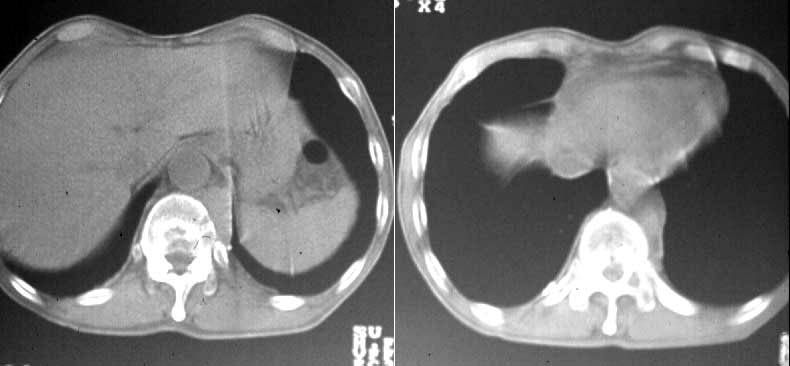

| 第196回定例研究会(1997.6) 骨シンチ『異常集積の少ない骨転移』 | 神奈川県立がんセンター | 小野 慈 |

(2)compartment解析に関しては代表的なものは、1-compartment model(秀毛らの非線形model(Fig.3)に始まるが、篠原が報告した如く線形modelでの短時間に演算可能な方法でも実用的であった。Veraらが唱えた3-compartment modelは採血を伴うmodel式を利用しており、やや煩雑さを伴っている。河らが提唱した5-compartment modelは複雑な計算式を必要としているが、肝最大除去率(Rmax)を算出可能である。(Fig.4)病的 hotなし。 | 第12胸椎に骨溶解像。 | 第12胸椎に 低信号域。 |

![]() | ![]() | ![]() |